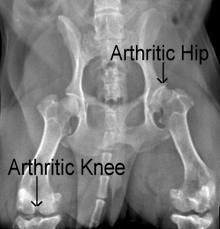

A thorough physical examination by a veterinarian can find areas of pain or reduced mobility. Taking an x-ray of the affected area can help to rule out other causes of significant joint or bone pain, such as fractures, dislocation, cancer, infection and ligament damage.